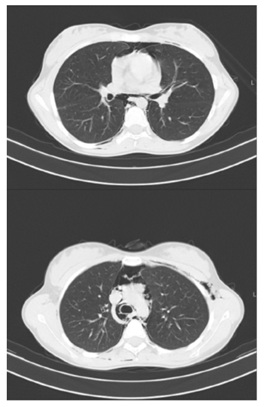

She underwent CT-Scan, which revealed widespread emphysema, that dissected the laterocervical mucle-aponeurosis plans from the skull base to the supraclavicular fossa, on the right, and the shoulders, on the left (Figure 2). The exam showed the presence of pneumomediastinum and bilateral pneumothorax (Figure 3).

Figure 3: Chest CT-Scan (axial, non-contrast) showing extensive pneumomediastinum and bilateral small blades of pneumothorax. No tracheal perforation. Heart and aorta within normal limits.